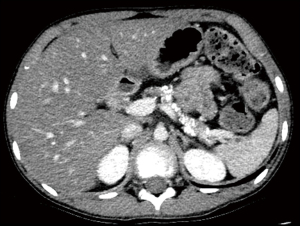

Initial laboratory findings, including complete blood count, liver function tests, CRP, amylase, and lipase, were unremarkable with a normal eosinophil count (4.3%, 450/µL). Fecal immunochemical testing was positive, and the fecal calprotectin (FC) level was 673 mg/kg. No pathogens were detected in stool culture or by multiplex polymerase chain reaction (PCR) (Seegene Inc.). Water’s view radiography demonstrated right frontal and bilateral maxillary sinusitis (Figure 1). Plain chest radiography demonstrated suspicious bronchiectatic lesions in both lung fields (Figure 2). Chest computed tomography (CT) demonstrated subsegmental atelectasis in the right middle lung field and diffuse bronchiectasis in both lungs (Figure 3). Abdominal CT and magnetic resonance (MR) enterography showed diffuse wall thickening from the distal ileum to the ascending colon. Pancreatic atrophy with diffuse calcification was observed with peripancreatic fat infiltration indicated chronic inflammation (Figure 4).

The clinical phenotype of this pair of siblings suggests p.Asp993Tyr is a pathogenic variant of the CFTR gene. Even this case presented with nonspecific symptoms, including chronic sinusitis and intermittent periumbilical pain; however, he had osteoporosis on bone densitometry and abdominal CT demonstrated pancreatic atrophic changes suggestive of CF. PERT, MCT, and lipid-soluble vitamin supplementation was provided to both patients based on failure to thrive, leading to improved growth chart and laboratory findings.